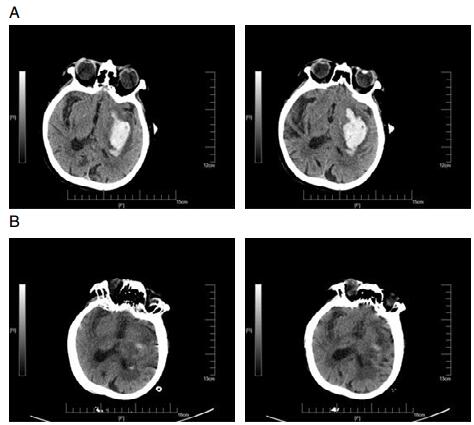

1.2 手术方法患者就诊后完善相关术前检查及准备工作。采用颅内血肿微创穿刺清除术,备皮后行CT定位,并避开颞浅动脉、颅内大血管(主要是外侧裂区及静脉窦)和重要功能区,根据CT图像,选取血肿最大层面,其上测量拟穿刺点头皮到血肿中心点的垂直距离选择相应长度的颅内血肿穿刺针(北京万特福公司生产的一次性使用颅内血肿清除套装)。床边监护、消毒、局麻后用尖刀片在拟穿刺点(血肿中心点在体表的投影点)切开头皮及皮下组织至颅骨,电钻钻穿颅骨后换上钝圆头针芯,手动将穿刺针插至血肿中心,拔除针芯,盖上螺帽,侧孔接引流管。第1次抽吸少于血肿的50%,抽吸完成后将穿刺针固定于颅骨部位,做好固定和标记;并注入尿激酶3~5万单位(溶解于5 mL生理盐水),注入后闭管2 h后开放,2次/d,必要时3次/d。手术过程中需注意抽吸时应使用等量生理盐水冲洗,以引流液清亮为标准,注意观察操作过程中患者生命特征变化并及时记录术中情况。根据每日引流量及术后CT判定拔针时间,拔管指征(一般2~3 d)有:术后复查CT提示颅内血肿清除大部(70%~80%)、引流液变少、颜色变浅变淡。

2 结果 2.1 三组患者血肿完全清除率及再出血发生率情况经过手术治疗后的三组患者,A组患者与B、C两组患者在血肿完全清除率上无明显差异,但是颅内再出血发生率明显低于B、C两组,差异具有统计学意义(P < 0.05,见表 1)。

3 讨论颅内出血是神经外科最常见的危急症之一,具有病死率高、致残率高、治愈率低的临床特点[10-12]。颅内血肿微创穿刺术在国内广泛开展,然而,不同穿刺时间点的选择对治疗效果的影响仍存在着争议[13-14]。本文为研究颅内血肿微创穿刺清除术治疗脑出血的最佳穿刺时间,回顾性对比分析了三组不同时间点手术患者的治疗效果,结果显示高血压脑出血患者超早期(4~6 h)行微创穿刺术,其术后再出血的发生率低于早期手术组及延期手术组,此研究结果和既往研究相反[15],可能与尿激酶超早期局部应用有关,也有可能超早期清除血肿,降低血肿对正常脑组织的不良反应及脑水肿的程度,具体分子机制有待进一步研究。同时超早期手术组患者平均住院时间明显短于早期手术组及延期手术组,术后随访结果显示超早期手术组的术后治疗效果明显优于早期手术组及延期手术组,超早期手术组中大多数患者能够在短期内恢复大部分的日常生活自理能力。